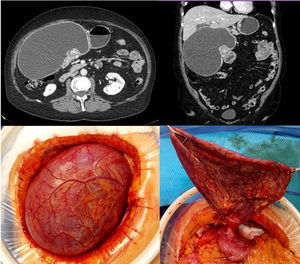

Mujer de 67 años de edad, estudiada por plenitud postprandial y pérdida de peso. Se le practica tomografía computarizada (TC) encontrándose una masa en antro gástrico de 18 x 10 cm compatible con quiste de duplicación. Fue intervenida realizándose una evacuación controlada del contenido y posterior sección del pedículo con endograpadora. El resultado anatomopatológico fue de proliferación fusocelular con estroma fibromixoide compatible con fibromixoma plexiforme. Se trata de una neoplasia mesenquimal benigna rara, descrita recientemente y de localización antral. Son propias del adulto de edad media, presentándose con clínica muy heterogénea y su diagnóstico diferencial debe realizarse con otras lesiones mixoides de la pared gástrica (fig. 1).